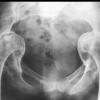

(三)X线检查:肠道钡剂检查有助于病损范围与性质的确定。但征象无特异性。钡剂灌肠示结肠粘膜呈细小的锯齿样边缘,皱壁不规则,肠壁僵硬或痉挛。有时可见肠段狭窄、溃疡和瘘管形成。少数溃疡边缘的粘膜可隆起,其X线征酷似癌肿,其鉴别点是病变段与正常肠段间逐渐移行而无截然的分界限,与癌肿不同。乙状结肠位置较低并折叠成角。应从不同角度摄片对鉴别病变性质有重要意义。 医学百科网 | YxBaike.Com

钡剂检查小肠,可见病变常以回肠末端为主。充钡时,可见管腔不规则狭窄,并因粘连而牵拉成角,形成芒刺样阴影,肠壁增厚、肠曲间距增宽。也可见肠腔结节样充盈缺损,与炎性肠病相似。排空时小肠正常羽毛状粘膜纹消失。近年来用肠系膜血管造影有助于发现小血管病变。对于放射性肠炎的早期诊断与鉴别诊断有一定意义。